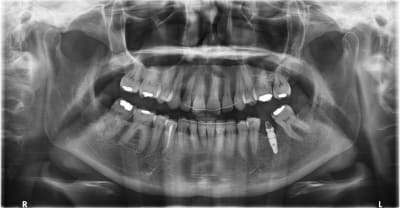

Je commence ci joint la pano

je sais juste que l'implant date d'environ 5 ans; la personne ne se rappelle pas qui lui a fait.

l'implant est conique, le col a des micros filets, l'apex est pointu, et la connexion est interne.

je pense pas que ça soit un dentaurum

le tiologic à une spire dédoublée et le tiolox n'a pas de microspire au col.

sur la radio la spire est simple et le col est microspiré

je me demande si c'est pas un paltop